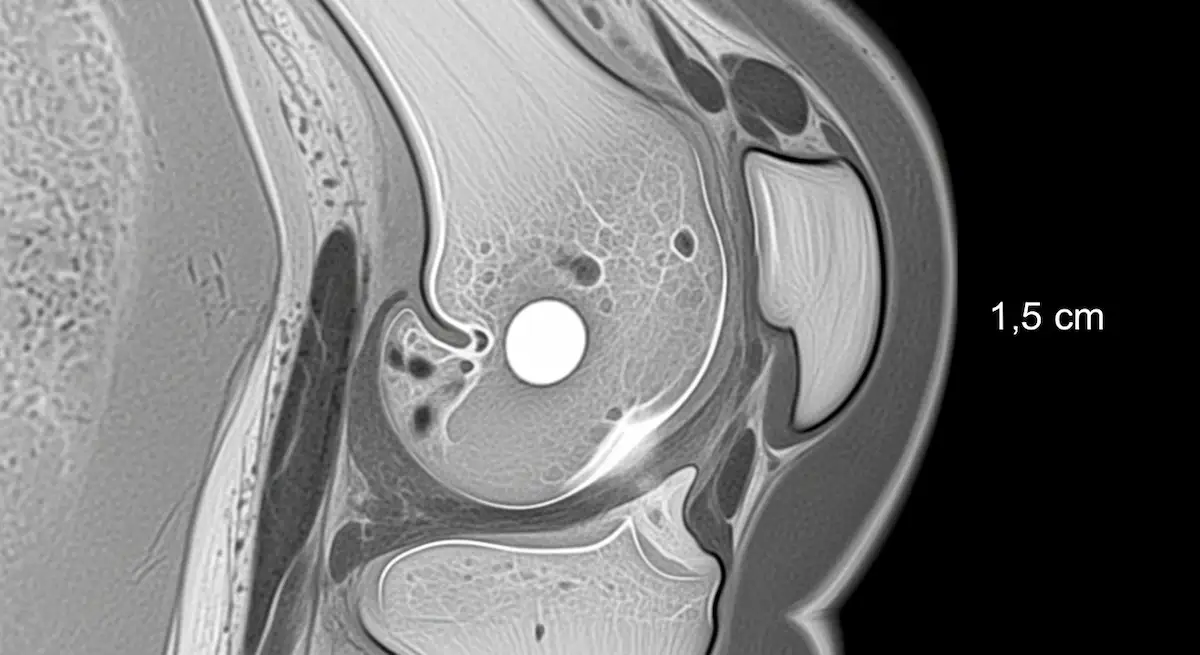

- A ressonância magnética confirma o cisto no menisco, mostra o tipo de lesão meniscal e afasta outras causas de dor, como cisto de Baker, cistos gangliônicos ou comprometimentos ligamentares.